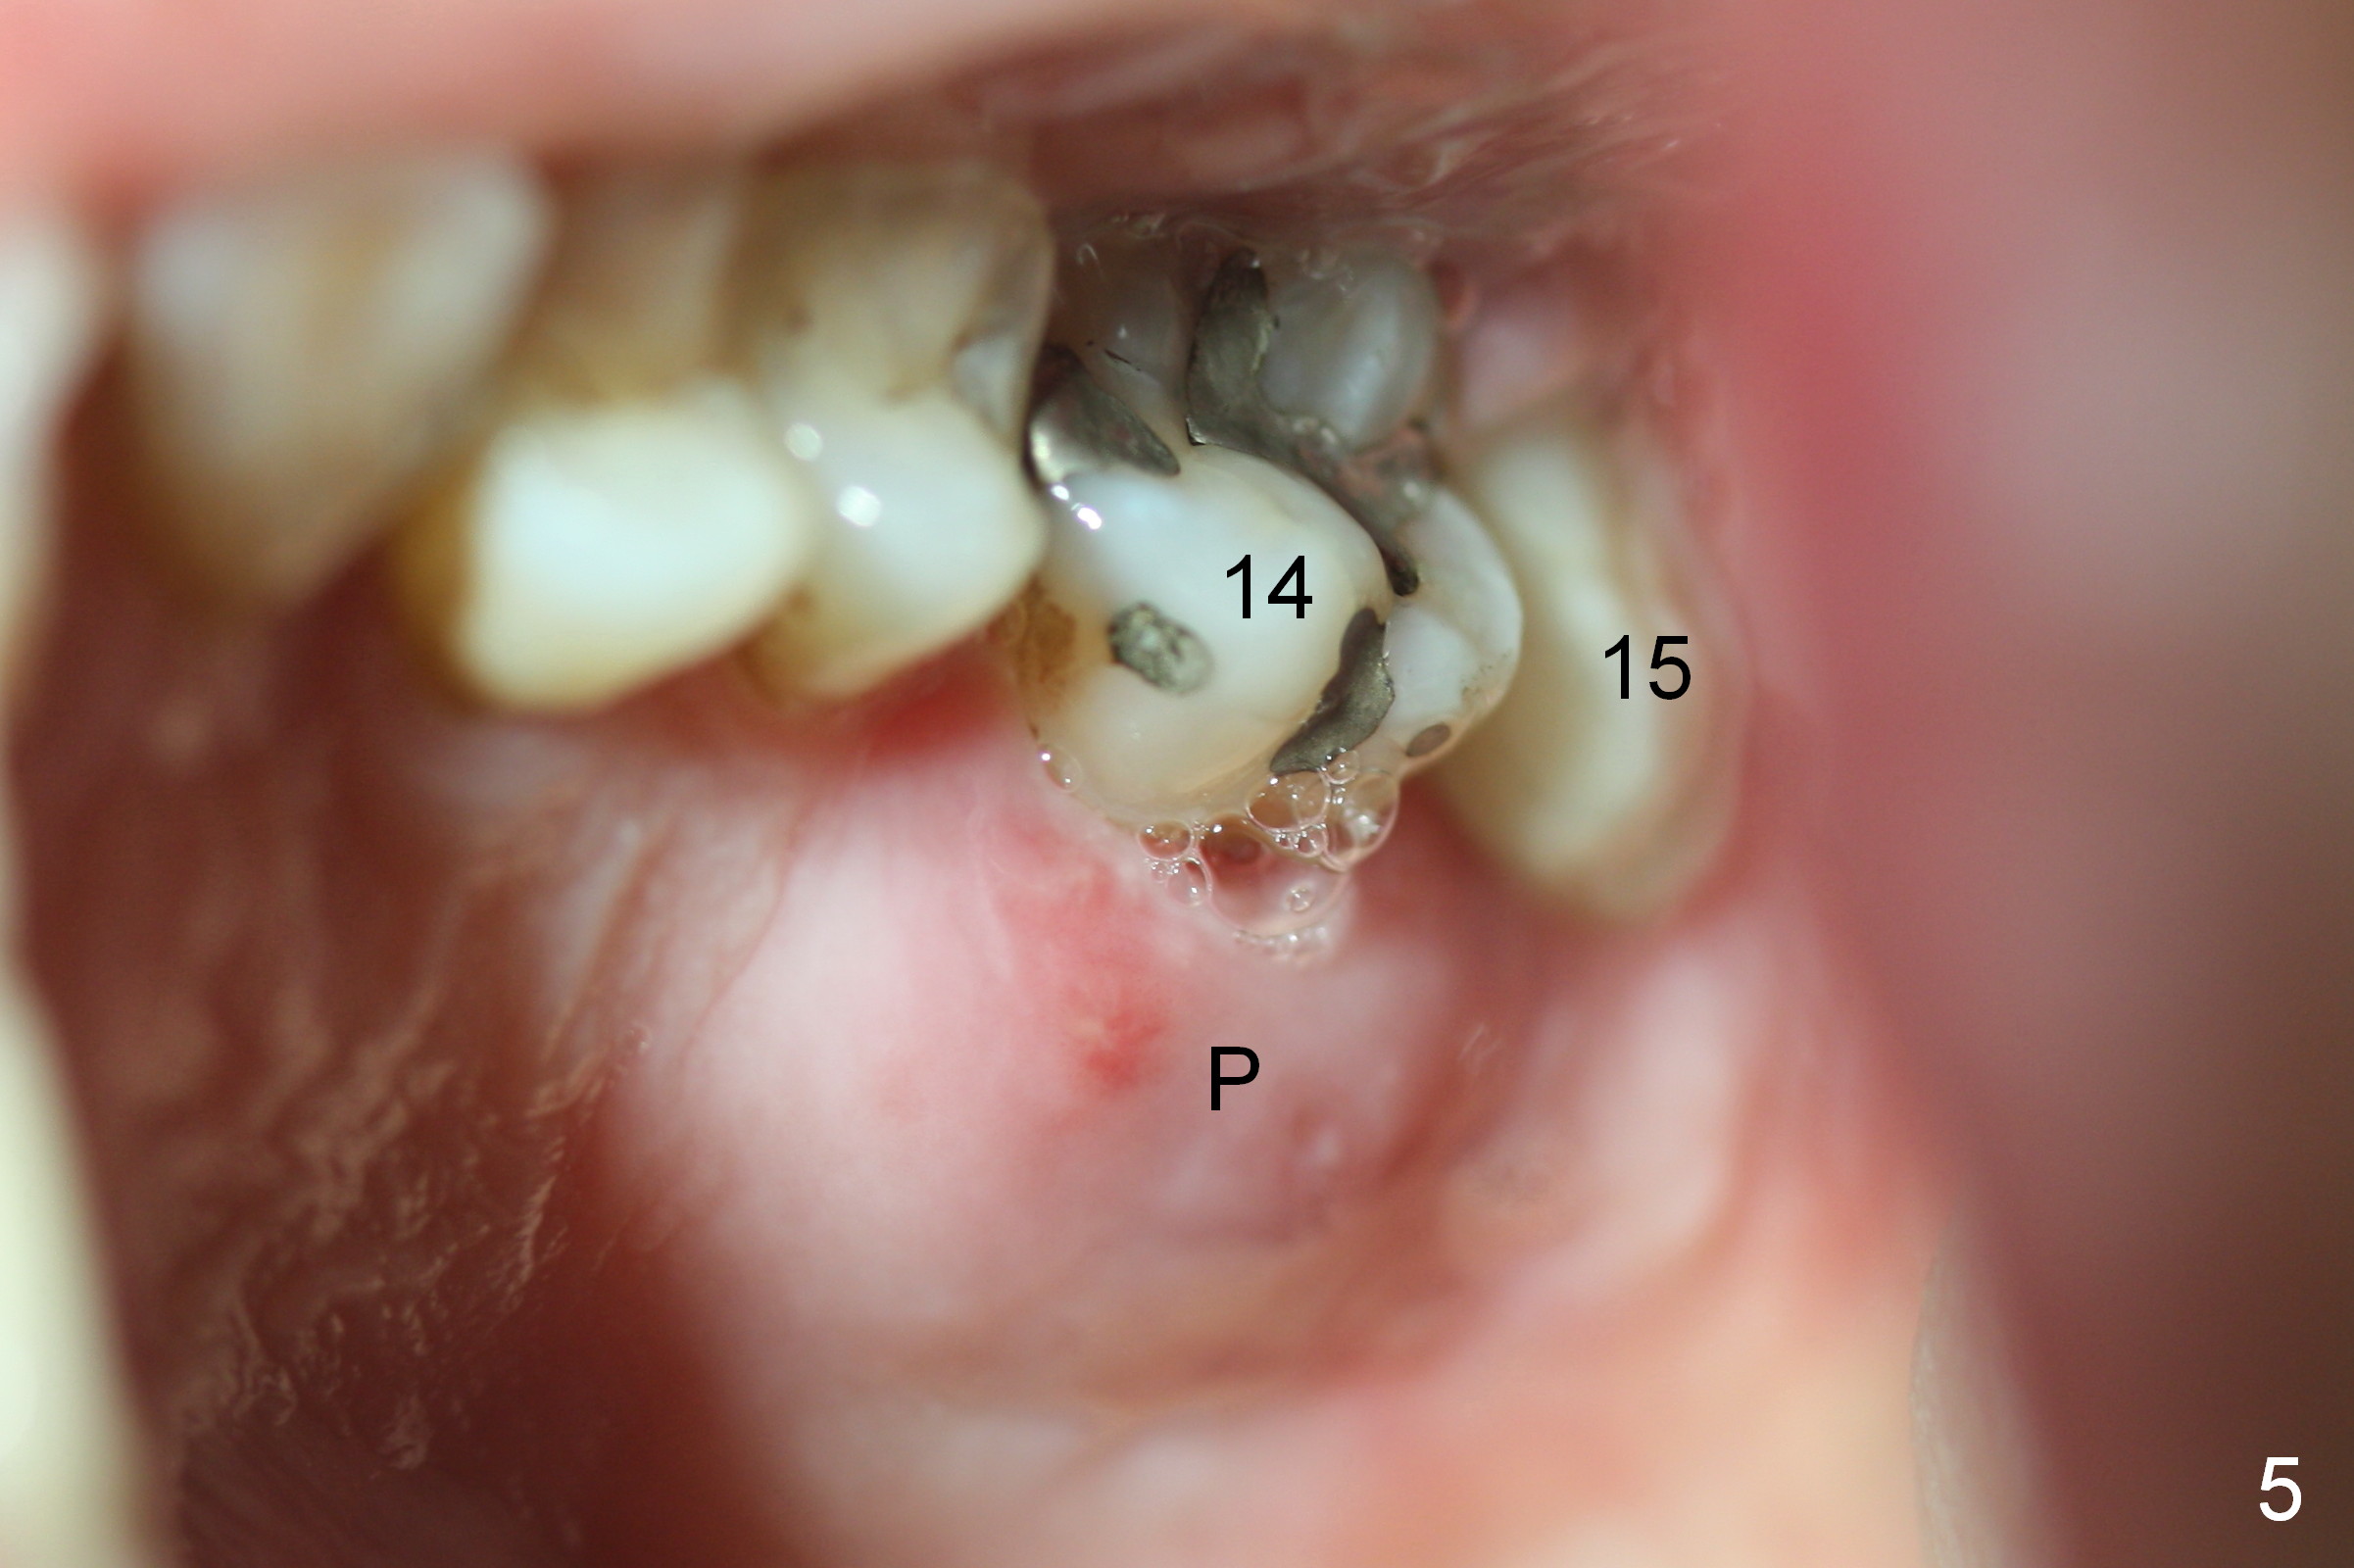

A 48-year-old lady has 4 relative contraindications to immediate implant: 1. infection is so severe at the site of #14 (the posterior maxilla with low bone density, Fig.4,5) that there is no enough bone to support the implant (Fig.7 illustration (1, 2); 2. dental insurance runs out; 3. she shows late in the afternoon when there is not enough staff; 4. she has had 2 immediate implants placed (Fig.4: #15 (3,4)). After socket preservation (Fig.8,9), she is most likely to return for implant placement.

It is noteworthy that the tooth #14 was less affected than #15 22 months earlier (Fig.1 (CBCT sagittal section), 2 (axial), 3 (coronal)). Calculus on the surface of the palatal root (Fig.6 P) is associated with the palatal abscess (Fig.5 P). S: septum.